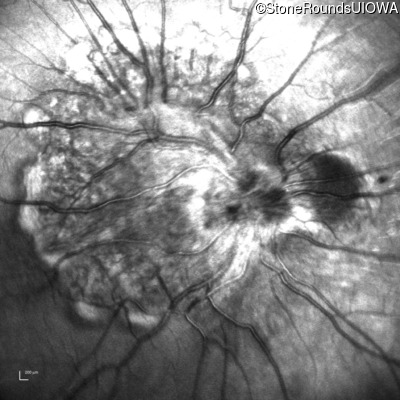

This 9 year old male was noted to have some crossing of his eyes at 2 months of age and the eye exam which followed identified a retinal lesion in the right eye. When he was six years old an epiretinal membrane was noted in his left eye. Two years later it was decided that it was a thin hamartoma in that eye as well. He underwent neuroimaging at age 7 which identified bilateral acoustic neuromas.

| Age at visit: 8 years |

| Age at visit: 10 years |

| Age at visit: 11 years |